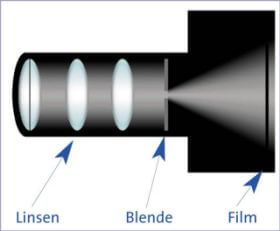

The structure of an eye is similar to that of a camera. Cornea functions like a lenses and it is a match for the front lenses of the camera objective. Pupil is like an amphibole of camera. And eye lenses are a match for other glass lenses in the camera objective. And finally, retina is like the film inside a camera.